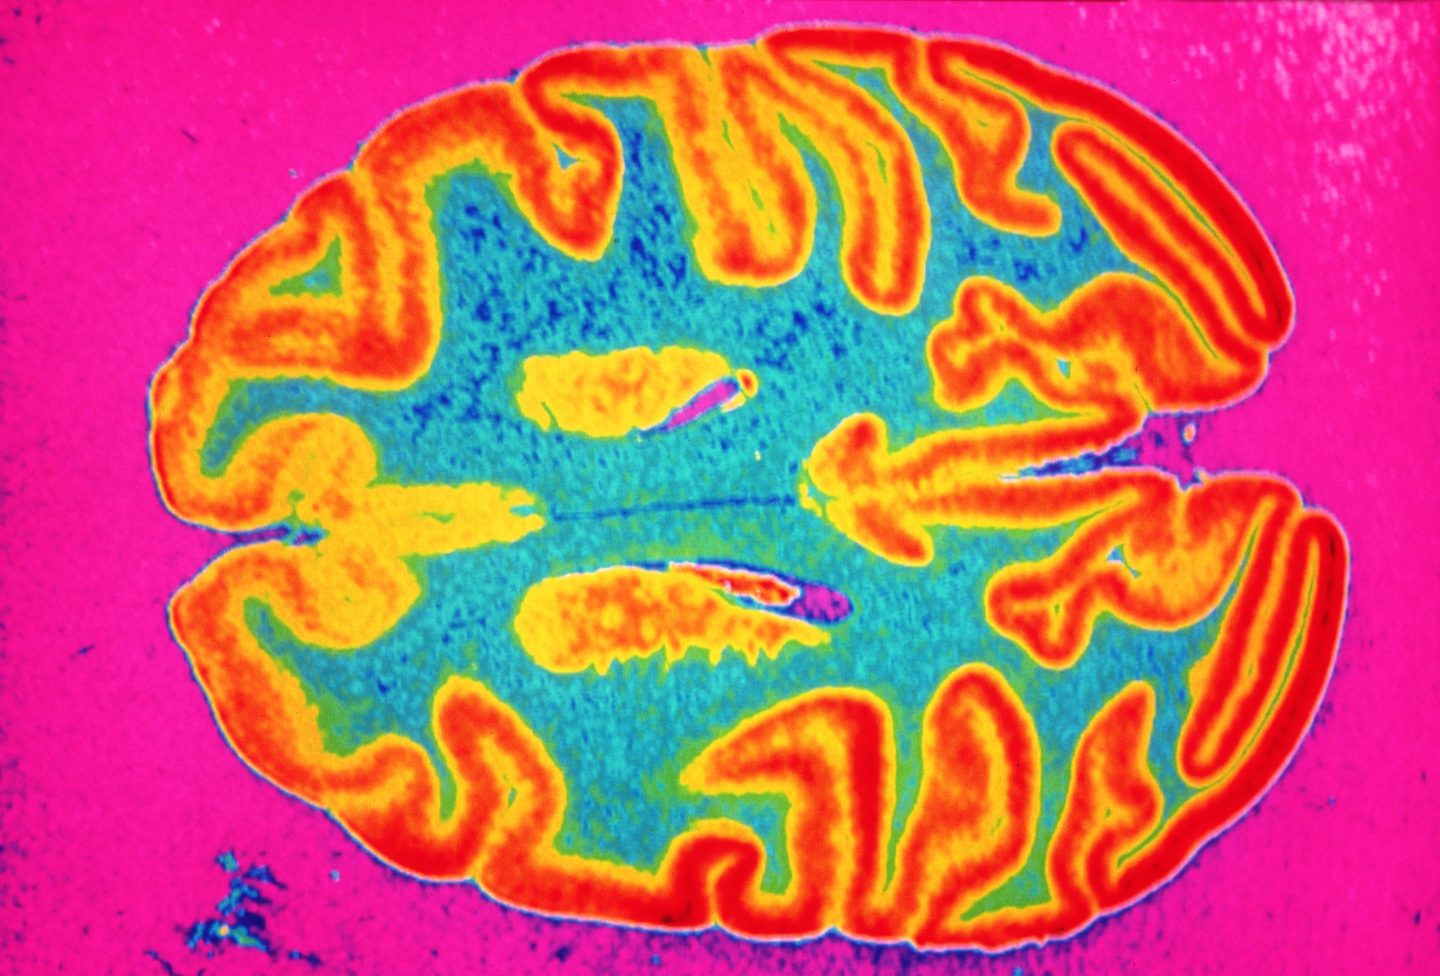

The study of 785 volunteers, aged 51 to 81, was conducted in conjunction with U.K. Biobank—an initiative to catalog the health information of half a million U.K. residents. Researchers compared two MRI scans of each subject’s brain, taken 38 months apart, with the first scan conducted before the pandemic began. In the intervening period, 401 of the volunteers had tested positive for COVID, providing a test and control group for the effects of the coronavirus on the brain.

Under normal circumstances, people lose about 0.2 to 0.3% of their brain matter each year through aging. Yet the study found that COVID patients experienced an additional loss of anywhere between 0.2 to 2% of their brain size in the three years between MRI scans. At worst, that is a loss equivalent to your brain shrinking over 10 years.

Only 15 of the volunteers who tested positive for COVID needed to be hospitalized due to the virus, meaning that even mild cases led to noticeable loss of brain matter.